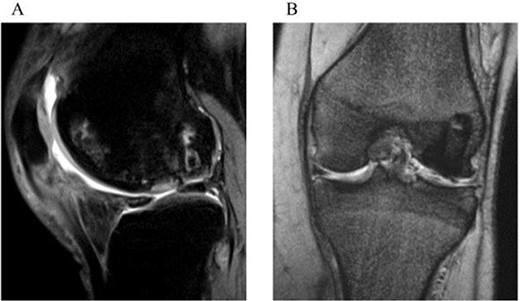

A 31-year-old female with SLE, who had been receiving oral steroid therapy since the age of 16, presented with severe pain in her left knee without any particular trigger. Physical examination showed local swelling and effusion in the left knee, and the passive ranges of motion for both extension and flexion were limited to −30° and 130°, respectively. Ligamentous instability or apparent malalignment was not noted. Radiographic examination of the knee showed flattened contour of the lateral femoral condyle and irregularity of the articular surface (Fig. 1a). MRI showed osteonecrosis extending from the lateral femoral condyle to the femoral trochlea, whereas a tear of the lateral discoid meniscus was also identified (Fig. 1b and c). A sagittal fat-saturated T2-weighted image of the contralateral right knee also showed osteonecrosis lesion in the lateral condyle (Fig. 1d). Based on those clinical and image findings, diagnoses of steroid-induced osteonecrosis of the femoral condyle and a tear of the lateral discoid meniscus were made. An urgent arthroscopy was performed as the patient was experiencing severe knee pain and limited extension of the knee because of detached osteochondral fragments and discoid meniscal tear. First, the ganglion connected to the anterior horn of the lateral discoid meniscus was resected, and a partial meniscectomy (meniscoplasty) was performed. A 35 × 45 mm cartilage defect was found in the lateral femoral condyle, and the detached osteochondral fragments were removed (Fig. 2a and b). After the removal of detached chondral lesions under arthroscopy, the limitation of the ROM and severe pain was resolved. However, a large osteonecrosis lesion with osteochondral defects remained, which presumably lead to secondary osteoarthritis. Therefore, OAT was planned as a second-stage surgery. At the OAT procedure, the contralateral knee could not be used for graft harvest because of the presence of osteonecrosis in the femoral condyle. Therefore, only two 10-mm diameter osteochondral grafts could be harvested from the non-weight bearing area of the medial femoral condyle in the ipsilateral knee, and then inserted into the recipient site (Fig. 3a and b). Since only part of the lesion area could be replaced by the host tissue, microfracture was performed in the remaining lesion. Postoperatively, ROM exercise was started immediately, whereas weight bearing was not permitted for the initial 4 weeks and gradually returned to full weight thereafter.

Arthroscopic findings. (a) Partially detached osteochondral fragment at the lateral femoral condyle. (b) Full-thickness cartilage defect after removal of the detached fragment.